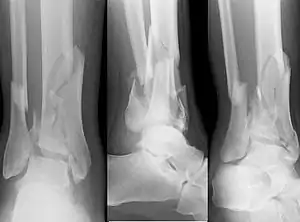

Pilon fracture

A pilon fracture, is a fracture of the distal part of the tibia, involving its articular surface at the ankle joint. Pilon fractures are caused by rotational or axial forces, mostly as a result of falls from a height or motor vehicle accidents. Pilon fractures are rare, comprising 3 to 10 percent of all fractures of the tibia and 1 percent of all lower extremity fractures, but they involve a large part of the weight-bearing surface of the tibia in the ankle joint. Because of this, they may be difficult to fixate and are historically associated with high rates of complications and poor outcome.[1][2][3][4]

| X-ray of a fracture involving the articular surface of the Tibia | |